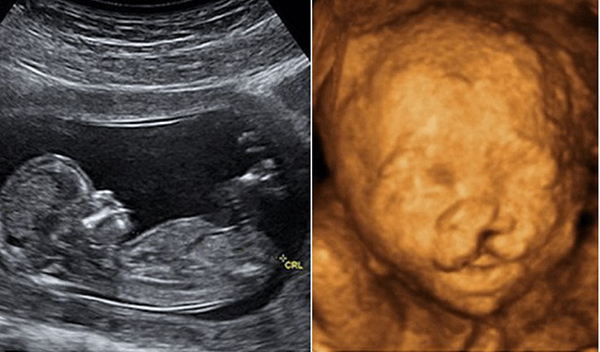

Siêu âm 3D

Là bước cải tiến từ siêu âm 2D ra đời vào năm 1980, hình ảnh thai nhi siêu âm 3D được chụp lần đầu tiên vào năm 1986. Siêu âm cho hình ảnh 3 chiều giúp cha mẹ có thể nhìn thấy hình ảnh của bé sống động hơn, thấy được cấu trúc mặt của bé qua hình ảnh màu.

Siêu âm 4D

Cho hình ảnh siêu âm 4 chiều có thể thấy được là sự chuyển động của bé qua đoạn băng ghi hình. Hình thức siêu âm này không chỉ giúp bác sĩ thấy rõ được những bất thường ở cấu trúc mặt, cơ quan sinh dục… mà còn là cách cha mẹ lưu giữ kỉ niệm cho bé.